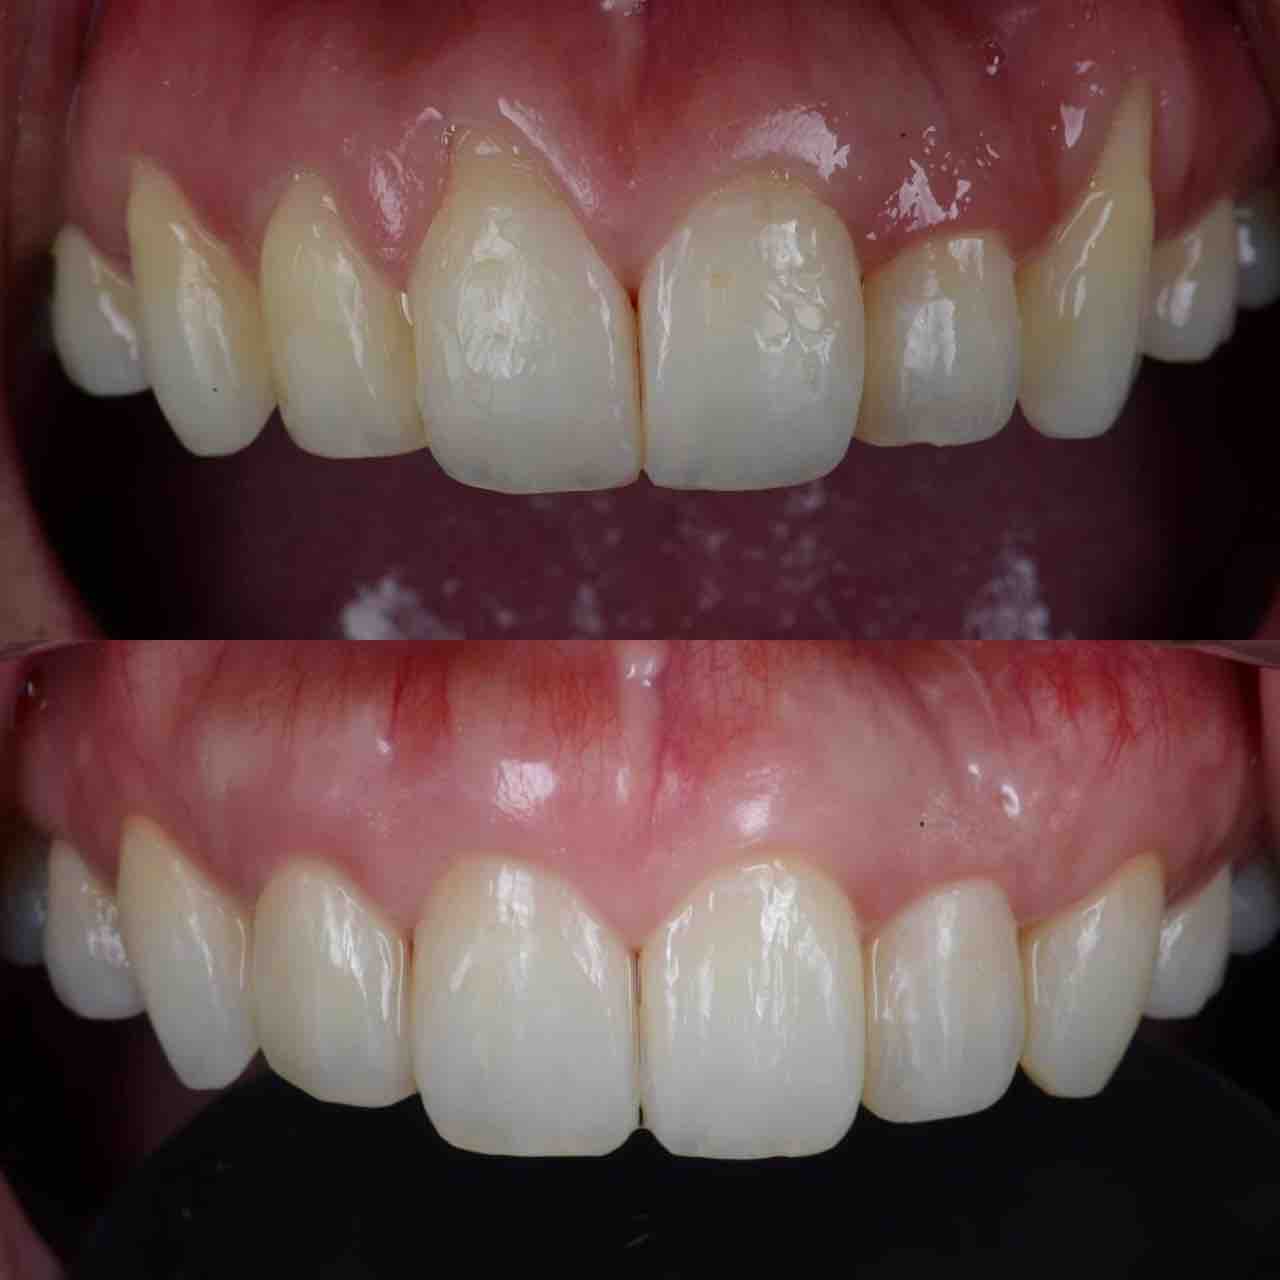

¥¤¥ó¥¹¥¿¥°¥é¥à¤ËºÜ¤»¤Æ¤¤¤ëÅö±¡¤Î¾ÉÎã¤Ç¤¹